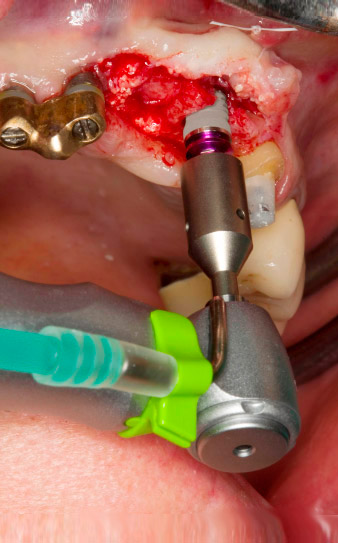

Following primary healing, the soft tissues were shaped using the basally lined bridge. Two months later the site was exposed by a slightly palatal alveolar ridge incision (Fig 2). The dimensions of the alveolar bone proved to be sufficient at position 22. Figures 2 and 4 show the preparation of the implant bed, the tapping and the implantation using Implantmed.

The new implantology motor was used with the appropriate W&H surgical contra-angle handpieces.